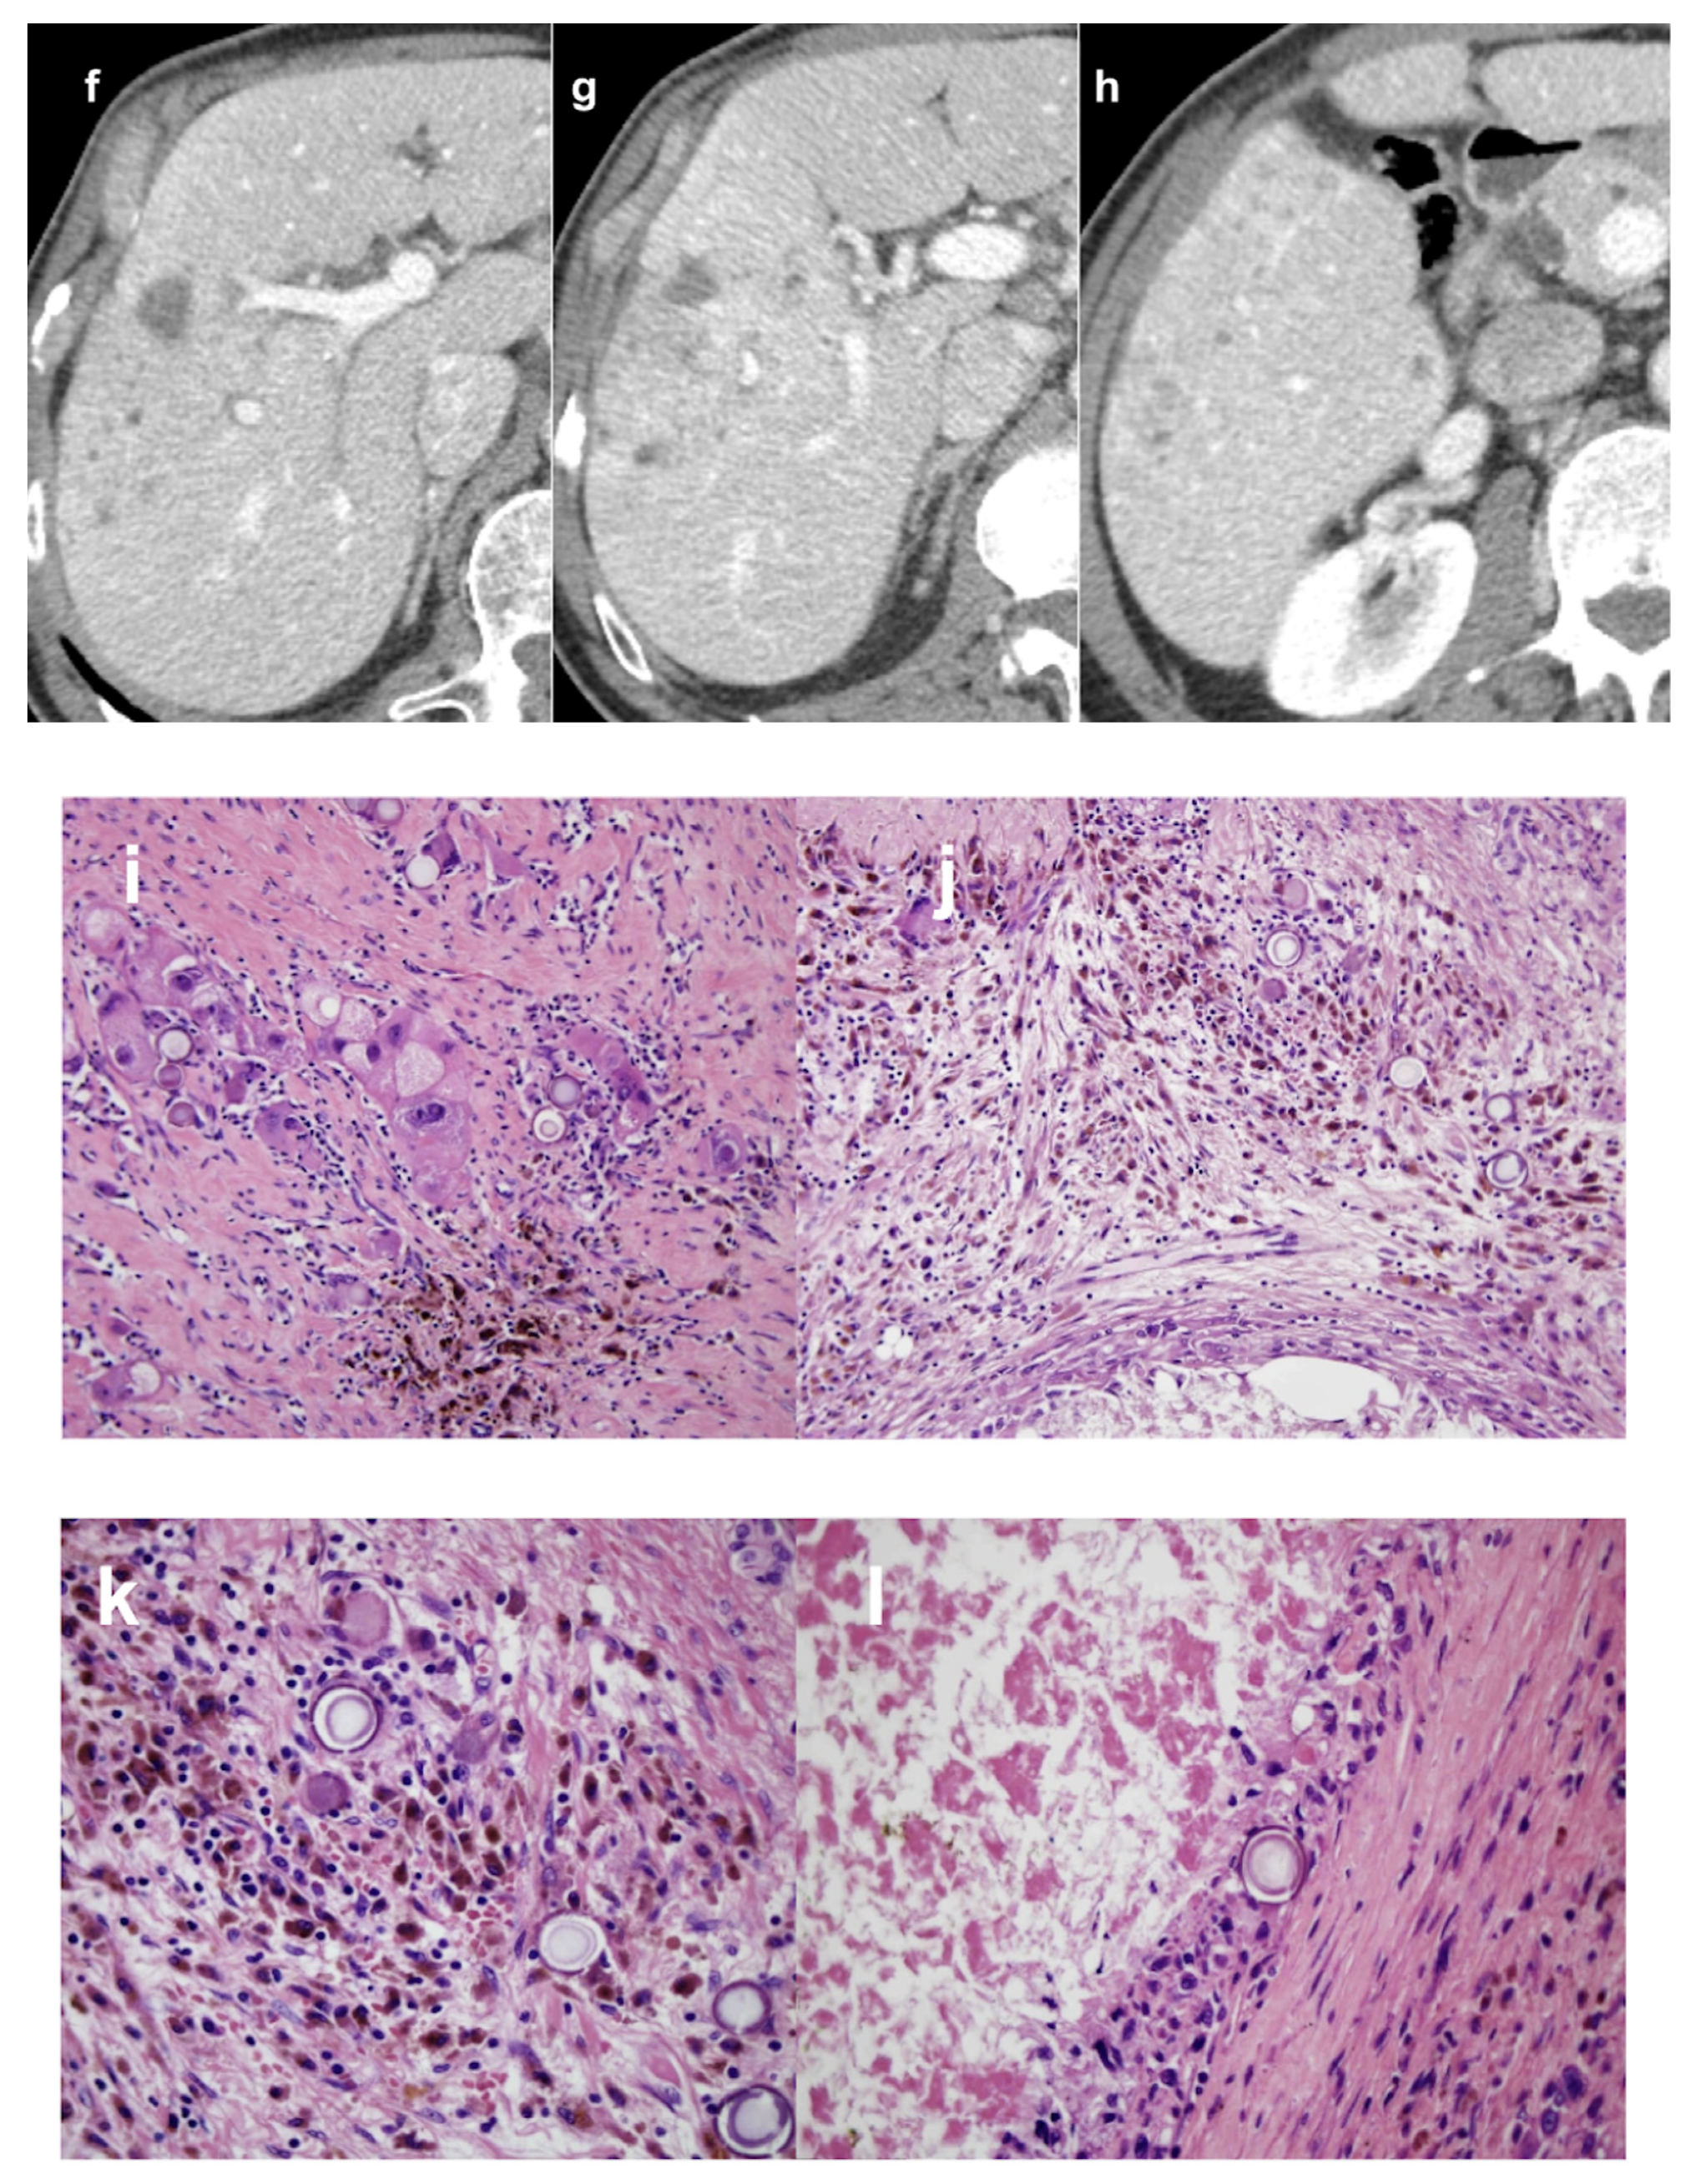

- Crocetti, L.; Scalise, P.; Bozzi, E.; Campani, D.; Rossi, P.; Cervelli, R.; Bargellini, I.; Ghinolfi, D.; De Simone, P.; Cioni, R. Microwave Ablation of Very-Early- and Early-Stage HCC: Efficacy Evaluation by Correlation with Histology after Liver Transplantation. Cancers 2021, 13, 3420. [Google Scholar] [CrossRef] [PubMed]